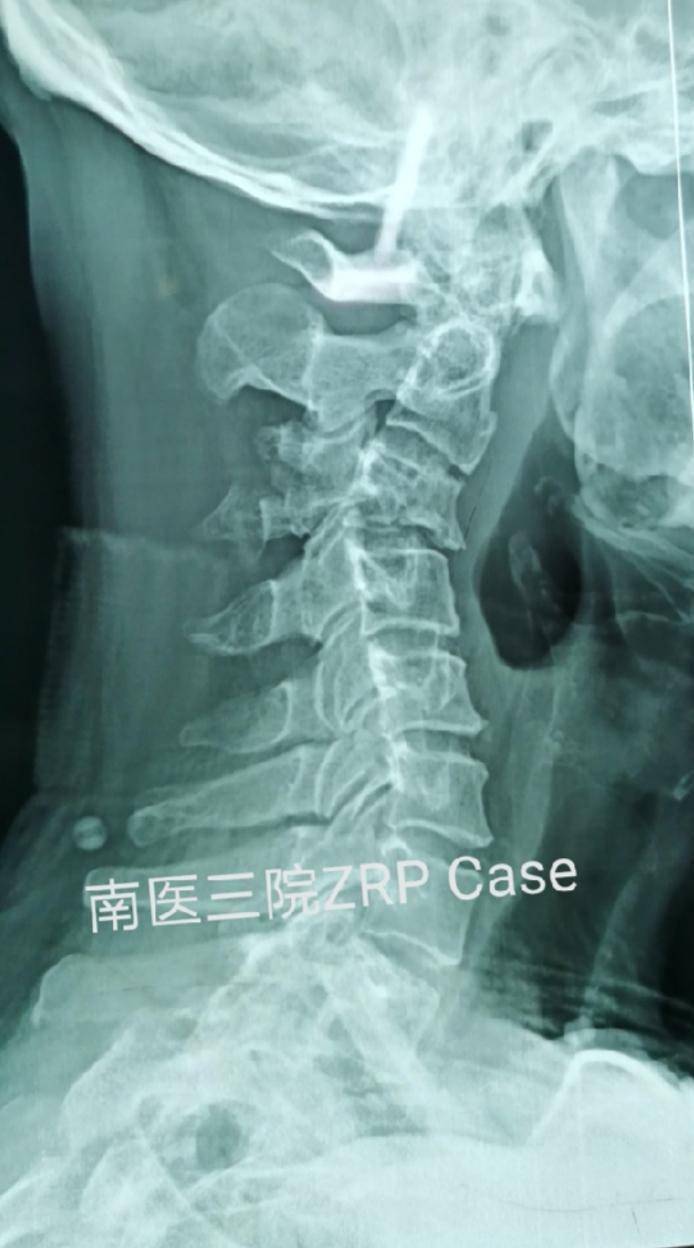

海宁小伙脖子竟"断了"!

图片尺寸996x664